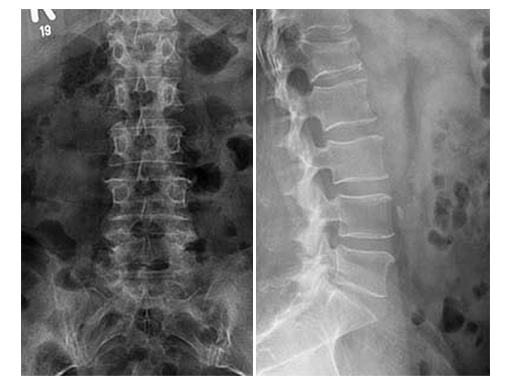

X-rays and CT scans were performed for preoperative analysis, definition of the fracture type and surgical pre-op planning.

The lateral x-ray and CT scans showed a typical wedge deformity of the fractured vertebral body (L1). The fracture included the cranial endplate as well as the anterior and posterior wall.

Additionally, a MRI scan was performed to analyze the integrity of the soft tissue in detail. The lateral MRI clearly showed a ruptured intervertebral disc at the level T12/L1.

Based on the Magerl Classification [1], the final classification of the fracture concluded in AO Type A 3.1.1. This fracture type is also referred to as an instable incomplete burst fracture including posterior wall involvement.